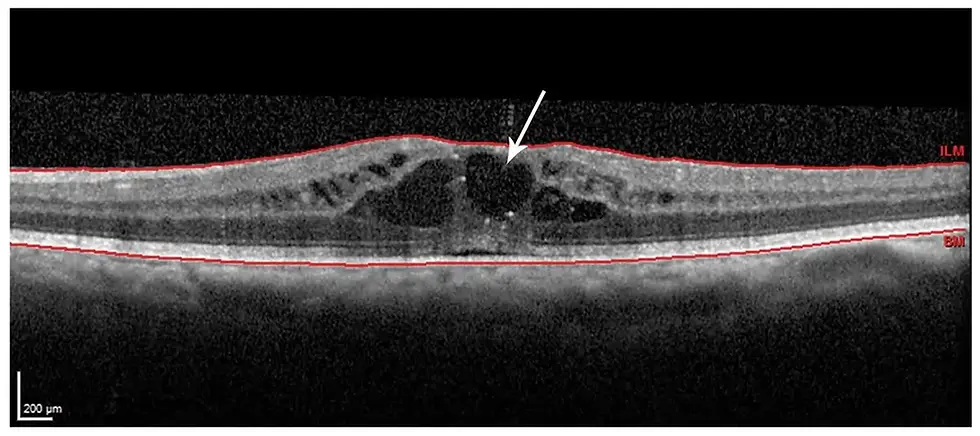

Tomografia de Coerência Óptica (OCT)

Exame não invasivo que avalia as camadas da retina e mostra se há fluido acumulado na mácula. Este é o método mais rápido e preciso para detectar o Edema Macular Cistoide.

A tomografia de coerência óptica (OCT) mostra o inchaço da mácula (edema macular cistoide) após a cirurgia de catarata, com acúmulo de líquido na região central da retina, causando visão embaçada Angiofluoresceinografia: